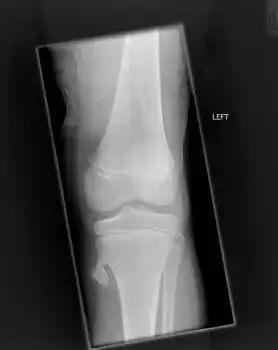

Osteochondroma arising from the thigh bone, near the knee